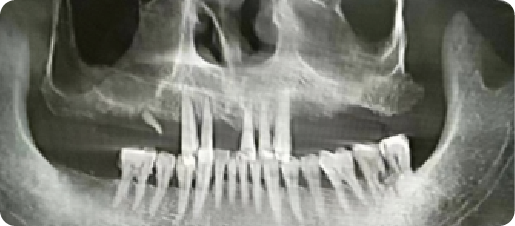

Case of Multiple Missing Teeth with Mobility of the Residual Dentition

BEFORE

VS

AFTER

Name:Mr NiuAge:64

Evaluation: Generalized tooth mobility and multiple tooth loss secondary to poor periodontal status

Treatment Plan:Two implants were placed in both the maxillary and mandibular anterior regions, each supporting two crowns, restoring a total of four teeth, a three unit fixed bridge, with a pontic for tooth #5, was supported by two implants in positions #4 and #6 in the upper left quadran.

Patient Feedback:It feels solid—I can bite with confidence, My healthy teeth were left alone, and they look so natural and feel so comfortable, it's just like having my own teeth back.